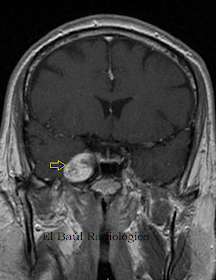

Mujer de 64 años. Schwannoma del tronco principal y ganglio de Gasser del trigémino derecho.

FIGURA 1-A) FSE-T1. Tumoración lobulada, hipointensa, que crece en la cisterna del ángulo pontocerebeloso (flecha amarilla) y se extiende hasta el cavum de Meckel (flecha amarilla).